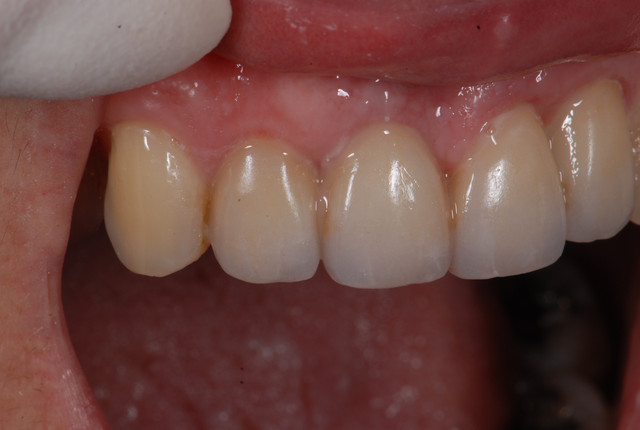

E.max crown try in 280713

#Togias 190713 nora